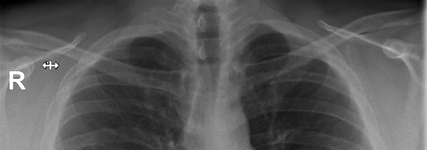

Wie wäre es mit einem Röntgenbild

Karten auf den Tisch

Eure körperlichen Gebrechen

Ich fange natürlich an

Mein größtes Problem ist wohl mein schiefes Becken.

Anhang anzeigen 10849686